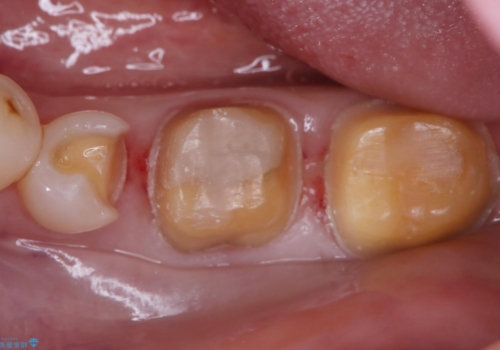

- ご友人との会話中などに、下の歯に入れてあるメタルインレーが見えてしまうのが気になり、やり変えを希望された患者様です。審美性、清掃性に優れたセラミックでの治療を希望されたため、セラミックインレー、クラウンで治療いたしました。